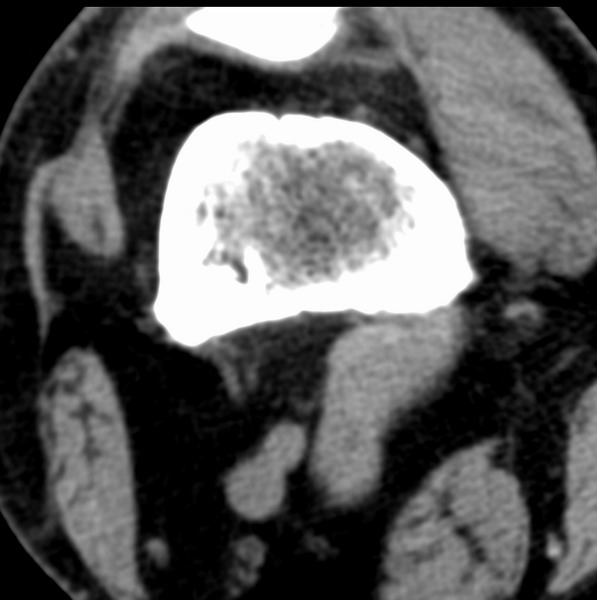

右侧膝关节疼痛一月

男、48

股骨下段、胫骨上段。

1、股骨干骺端病变考虑干骺端纤维性皮质缺损愈后(非骨化性纤维瘤)改变,胫骨近端内生骨瘤(或干骺端纤维性皮质缺损愈后改变);

2、骨关节炎,骨质增生,股骨外侧髁退变性囊肿(关节面软骨下囊肿);

多发内生软骨瘤!

股骨干骺端病变考虑非骨化性纤维瘤。

1、股骨干骺端病变考虑干骺端纤维性皮质缺损愈后(非骨化性纤维瘤)改变,胫骨近端内生骨瘤;